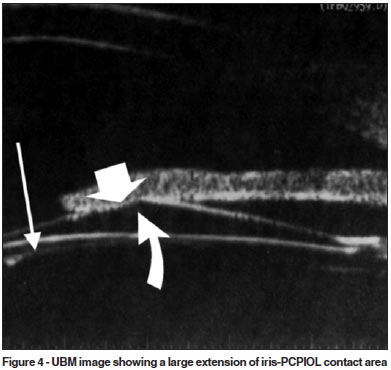

It is known that pupillary block mechanism is the cause of acute angle closure in eyes which a posterior chamber phakic intraocular lens (PCPIOL) implantation is performed for correction of high myopia(29-30). This only occurs in eyes without LPI prior to the PCPIOL implantation. Figure 4, an UBM image, demonstrates a true case of pupillary block (IOP was 45 mmHg 20 hours after PCPIOL implantation). It occurred in a patient without LPI due to a large extension of iris-PCPIOL contact area which prevented the aqueous humor flow to the anterior chamber. In this case, the extension of the iris-PCPIOL contact area was 2.580 mm and the ILA was 16.03 (arcdegree). These values are much higher than those found in eyes with APAC after LPI under light conditions. An LPI resolved the pupillary block.